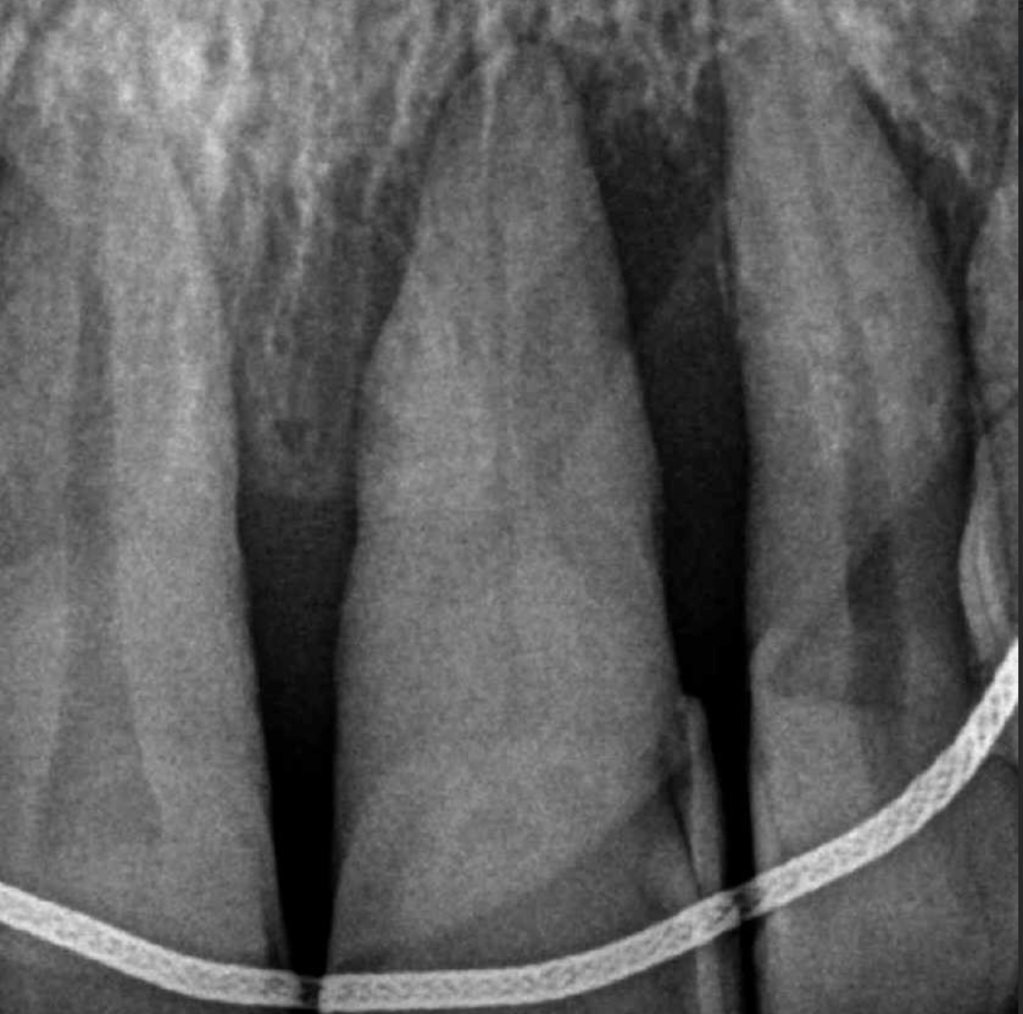

Pulpotomía biodentine + reco preendio